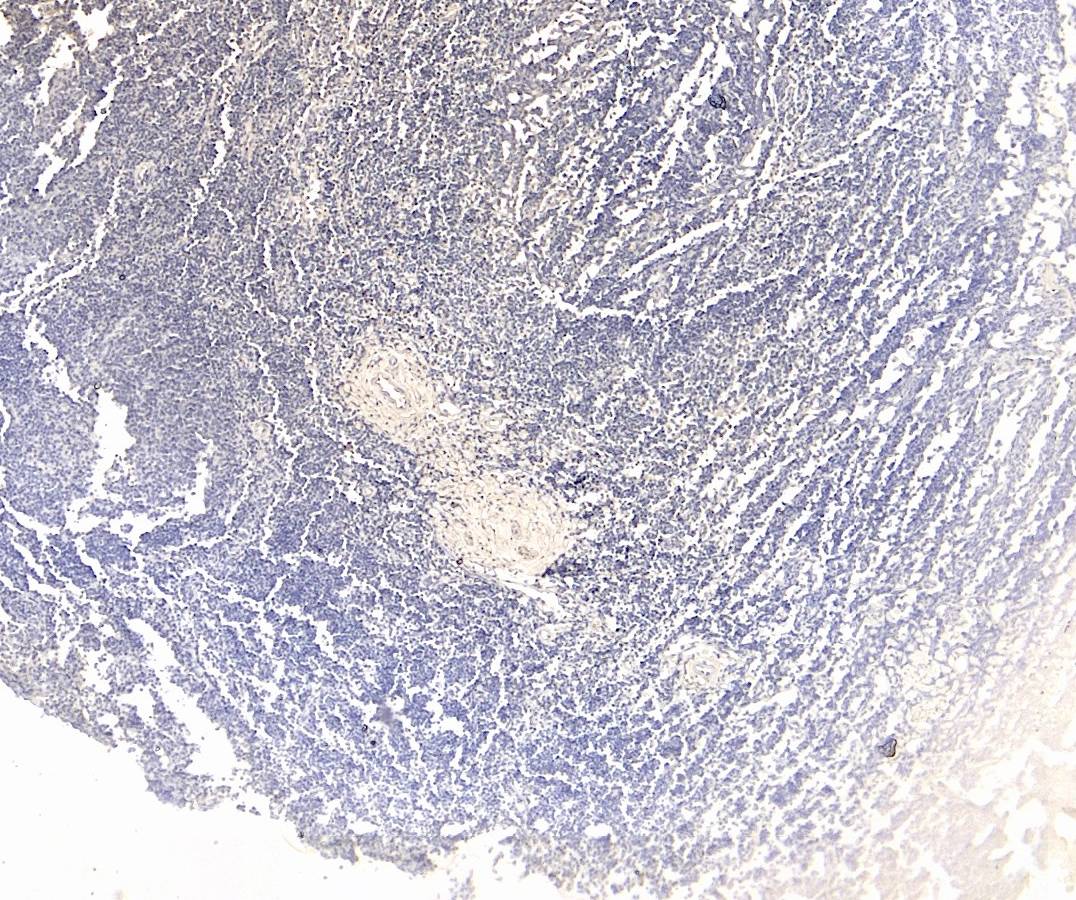

IHC Results Paraffin embedded Human Tonsil. Recommended concentration: 4µg/ml. | |